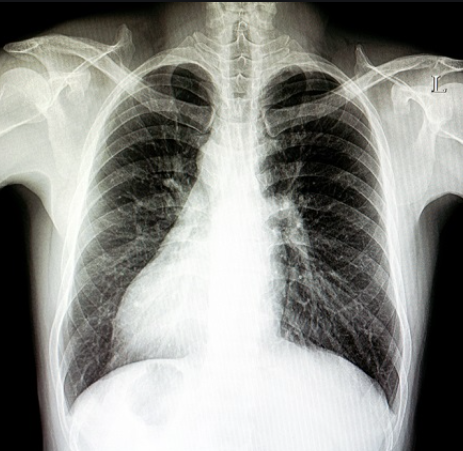

(i) X-ray images of the entire human body

1. An X-ray is a quick and painless procedure commonly used to produce images of the inside of the body. It’s a very effective way of looking at the bones and can be used to help detect a range of conditions.

2. X-rays can be used to examine most areas of the body. They’re mainly used to look at the bones and joints, although they’re sometimes used to detect problems affecting soft tissue, such as internal organs.

3. The X-ray machine, which looks like a tube containing a large light bulb, will be carefully aimed at the part of the body being examined by the radiographer.

Note: The benefits and risks of having an X-ray will be weighed up before it’s recommended. Talk to your doctor or radiographer about the potential risks beforehand, if you have any concerns. The skeleton comprises the skull, the backbone, ribs and the breast bone, shoulder and hipbones, and the bones of hands and legs.